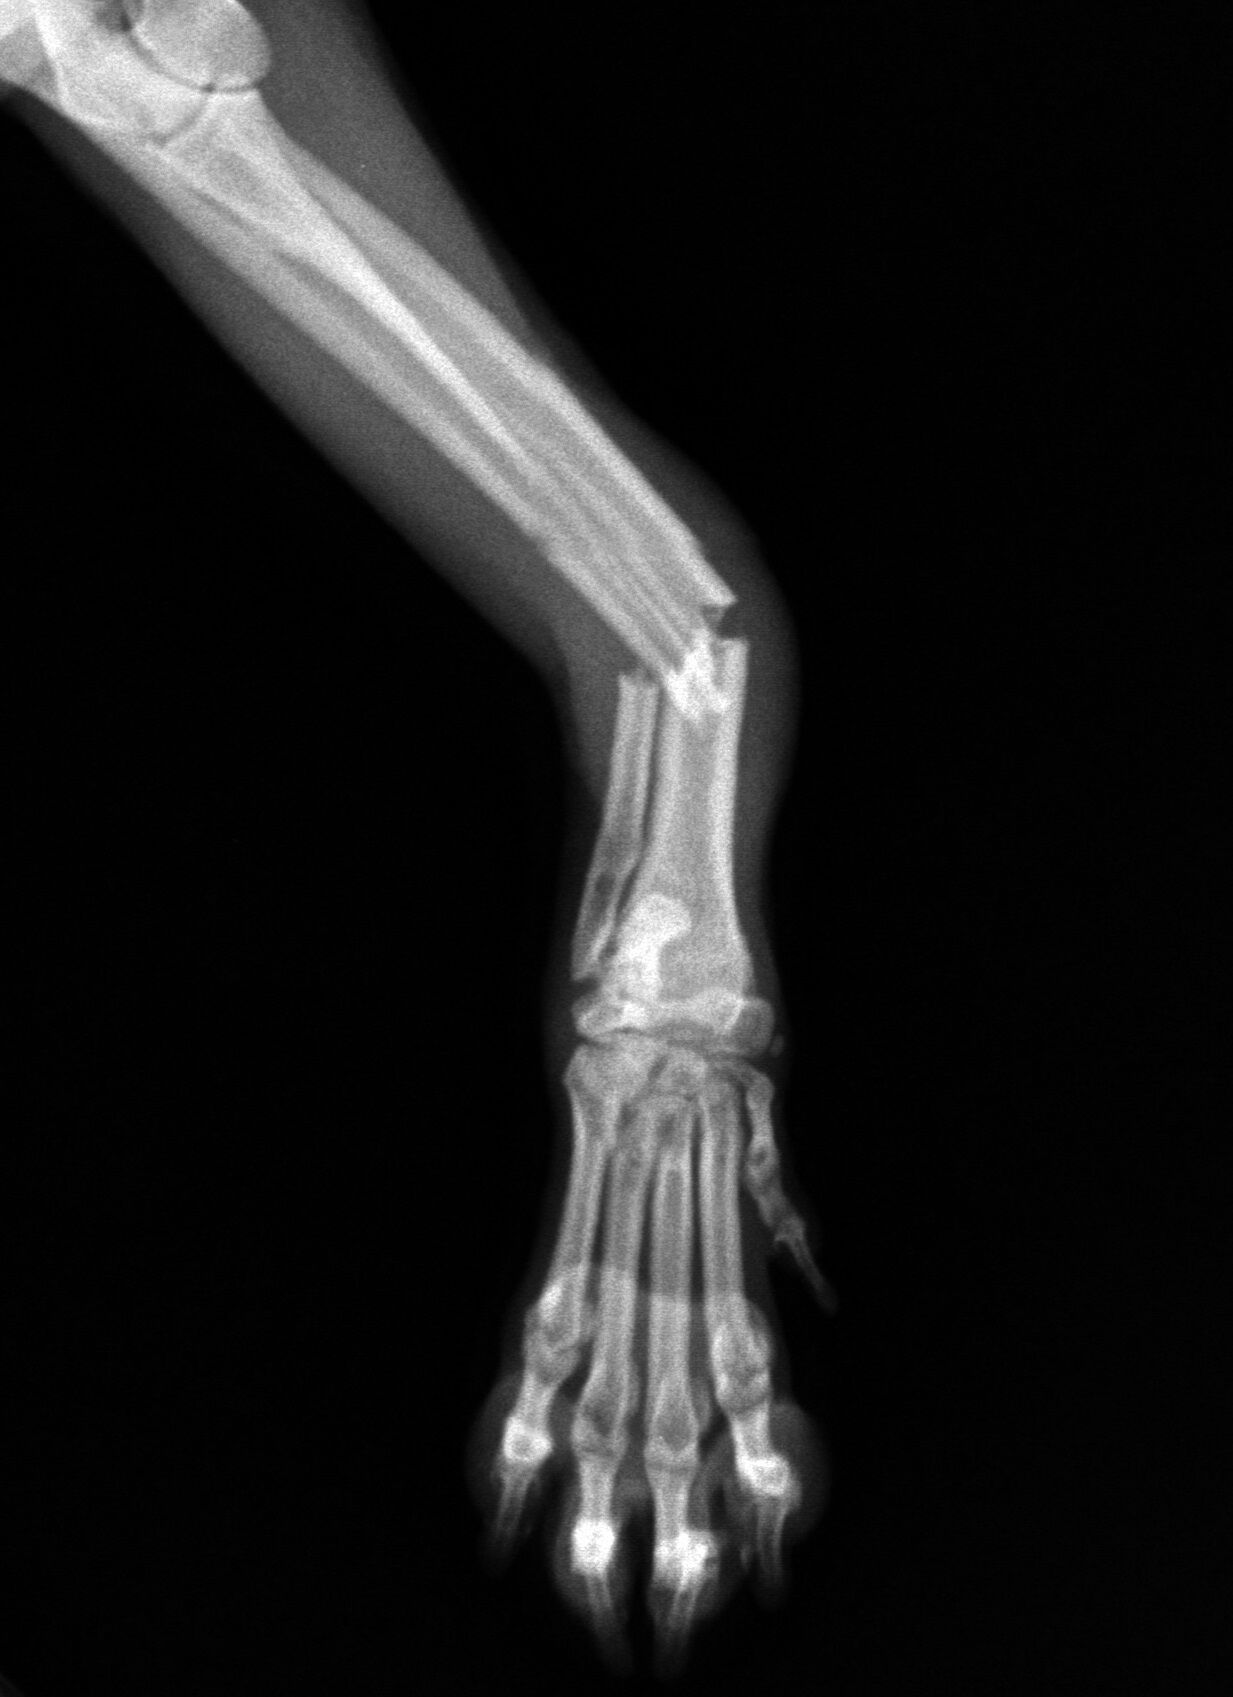

今回は1歳の柴犬の骨折治療です。お子さんが抱っこしていて降ろす際に

着地に失敗して右橈尺骨を骨折してしまいました。